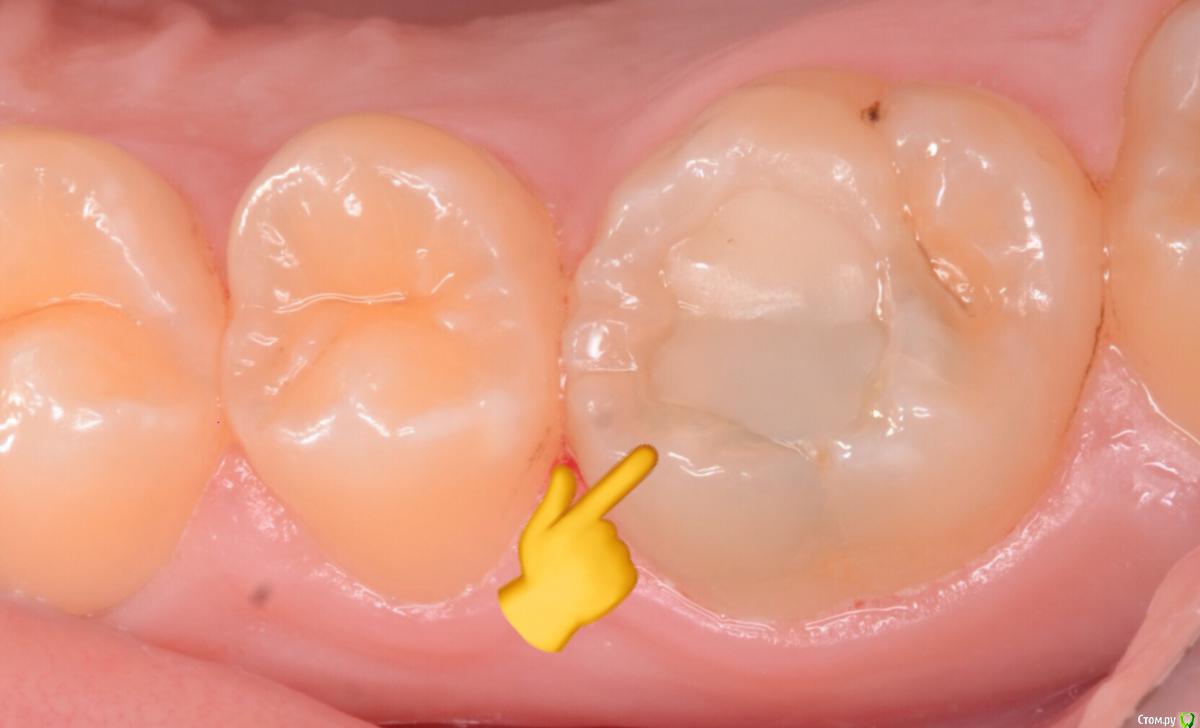

CRAZYDUCK Опубликовано 3 декабря, 2018 Автор Поделиться Опубликовано 3 декабря, 2018 Девочка , 12 лет . Это единственный зуб , который нуждался в лечении . На снимке RVG виден размер кариозной полости , верхушка корня не закрыта . Вскрытый рог закрываем МТА, йоносит и реставрация эстелайт ОА2, А1, краситель для фиссур. Ссылка на комментарий

CRAZYDUCK Опубликовано 3 декабря, 2018 Автор Поделиться Опубликовано 3 декабря, 2018 Это точка вскрытия .Теперь наблюдение - холодовая проба и rvg каждые 3-4 месяца до закрытия апекса . Ссылка на комментарий